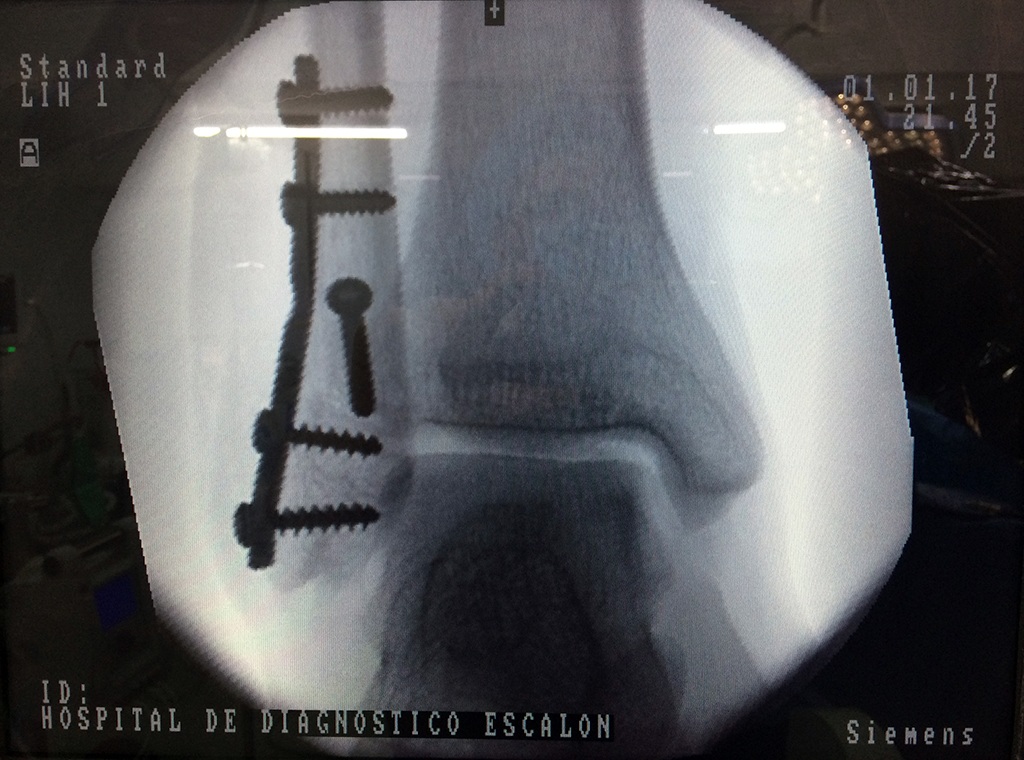

Cuando se necesita cirugía, es probable que esta implique el uso de clavijas de metal, tornillos o placas para sostener los huesos en su lugar mientras la fractura se consolida. Los elementos de soporte pueden ser temporales o permanentes.